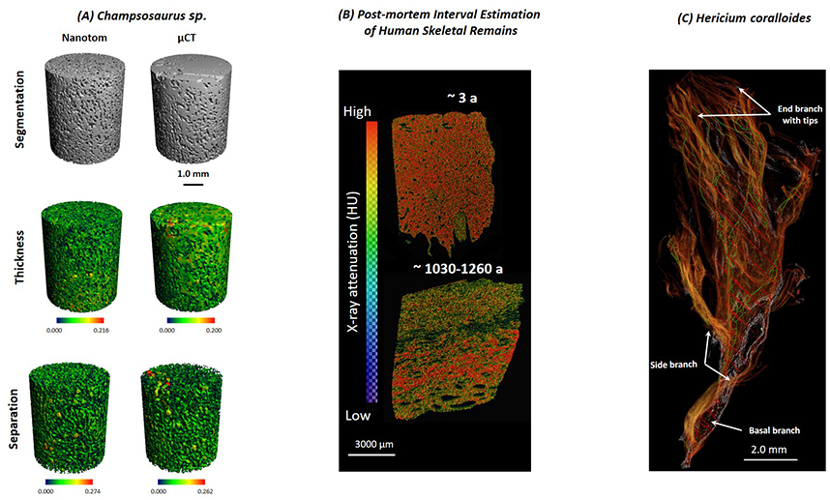

Research applications include fracture healing, skeletal phenotyping, segmental bone defect repair, age-related effects on bone, joint degeneration, tumour infiltration, developmental biology and the microstructure of materials. Both micro-CT scanners can be used for the high-resolution imaging of small animals (ranging from mice to rabbits). The XtremeCT II is also used for high-resolution scanning of patient extremities and primarily for the evaluation of bone density and micro-architecture in the scaphoid bone. The power of these systems lies in their capacity for users to extract quantitative morphometric and density data along with 3D models of their specimens.

- C. Wöss, S. H. Unterberger, G. Degenhart, A. Akolkar, R. Traxl, V. Kuhn, M. Schirmer, A. K. Pallua, R. Tappert, J. D. Pallua: Comparison of Structure and Composition of a Fossil Champsosaurus Vertebra With Modern Crocodylidae Vertebrae: A Multi-Instrumental Approach. J Mech Behav Biomed Mater (2020):104:103668. DOI: 10.1016/j.jmbbm.2020.103668.

- S. Longato, C. Wöss, P. Hatzer-Grubwieser, C. Bauer, W. Parson, S. Unterberger, V. Kuhn, N. Pemberger, A.K. Pallua, W. Recheis, R. Lackner, R. Stalder, J D Pallua: Post-mortem Interval Estimation of Human Skeletal Remains by Micro-Computed Tomography, Mid-Infrared Microscopic Imaging and Energy Dispersive X-ray Mapping. Analytical methods. 02/2015; 7(7). DOI:10.1039/C4AY02943G

- J D Pallua, V. Kuhn, A.F. Pallua, K. Pfaller, A.K. Pallua, W. Recheis, R. Pöder: Application of micro-computed tomography to microstructure studies of the medicinal fungus Hericium coralloides. Mycologia 11/2014; 107(1). DOI:10.3852/14-188